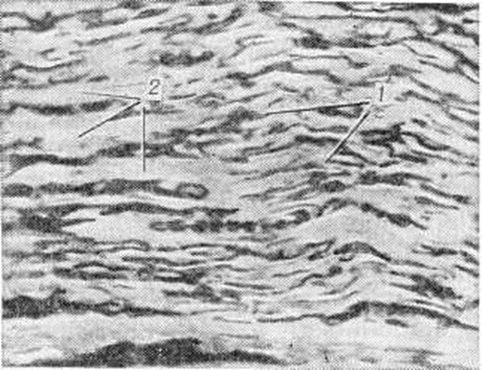

Дифтерийная интоксикация характеризуется поражением нервной, сердечно-сосудистой систем, надпочечников и почек. С большим постоянством выявляются изменения в узлах симпатической части высшая нервная система, где, помимо сосудистых расстройств, обнаруживается более или менее выраженная дегенерация ганглиозных клеток. Поражение периферических нервов проявляется множественным токсическим невритом (смотри полный свод знаний Невриты). Отмечается повреждение нервных оболочек, и прежде всего миелиновой оболочки — деструктивные изменения в ней нередко достигают полного распада и гибели миелина (рисунок 2). В миелиновой оболочке происходит пролиферация клеточных ядер. В меньшей степени изменяются осевые цилиндры; обычно лишь часть их подвергается деформации и распаду.

Наиболее глубокие дегенеративные изменения отмечаются в миокарде — паренхиматозное перерождение мышечных волокон вплоть до полного миолиза, глыбчатый распад (рисунок 3) или диффузное дегенеративное ожирение. Методом иммунофлюоресценции (смотри полный свод знаний) в больших мононуклеарах и поражённых миофибриллах обнаруживается дифтерийный токсин. Электронно-микроскопическое исследование (смотри полный свод знаний Электронная микроскопия) выявляет выраженные изменения ультраструктуры: нарастающую деструкцию митохондрий, жировую дистрофию (смотри полный свод знаний), а позже очаговую деструкцию миофибрилл. Гистохимически определяются значительные нарушения в системе внутриклеточных энзимов, определяющих активность окислительных процессов (Берч (G.E. Burch)], Гур и Паппенгеймер (R. S. Gour, А. М. Pappenheimer, 1967) указывают, что патогенное действие токсина на ткани связано с инактивацией внутриклеточного фермента амино-ацил-трансферазы II, принимающей участие в белковом обмене. Зелингер (С. В. Saelinger, 1973) экспериментально установил значительную задержку синтеза белка в поражённом токсином миокарде. Таким образом, в результате непосредственного действия токсина, подавляющего активность энзимных систем, происходят глубокие нарушения обменных процессов в миокарде. Исходом острого миокардита иногда может явиться выраженный диффузный склероз миокарда (смотри полный свод знаний Кардиосклероз).